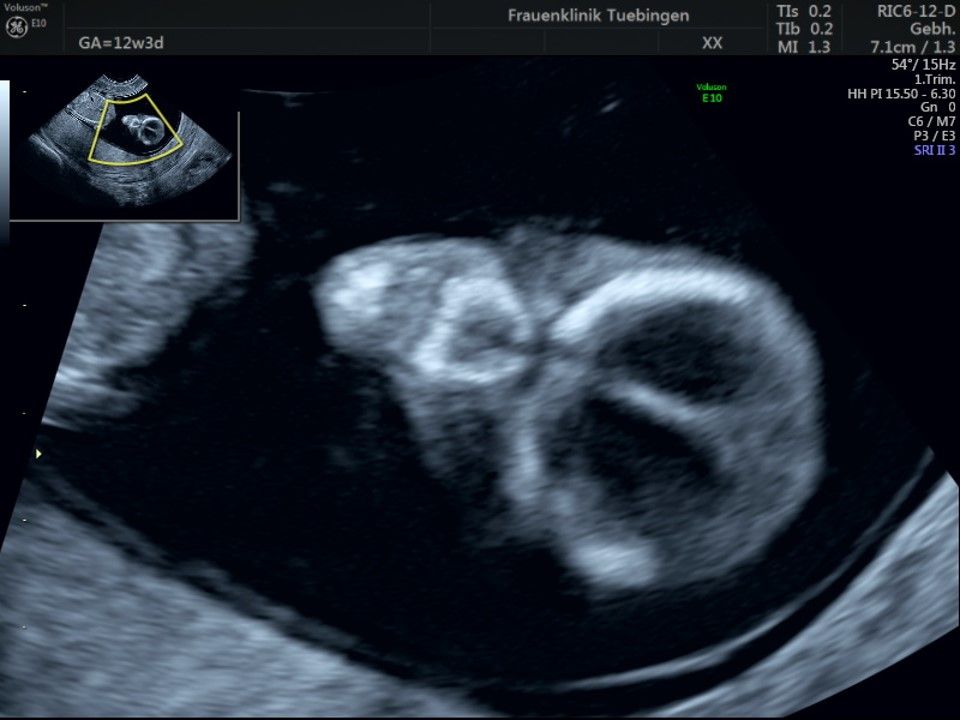

Im Rahmen des Ersttrimester-Screenings untersuchen wir die Organe des Feten mittels Ultraschall. Dabei machen wir auch gerne ein Bild für Sie.

Obwohl der Fet zu diesem Zeitpunkt erst zwischen 5 und 8cm groß ist, lassen sich bereits etwa die Hälfte aller schwerwiegenden Fehlbildungen erkennen bzw. ausschließen. Sollten wir eine Auffälligkeit sehen, werden wir mit Ihnen den Befund und das weitere Vorgehen ausführlich besprechen.

Fetale Anatomie

Bauchwanddefekt